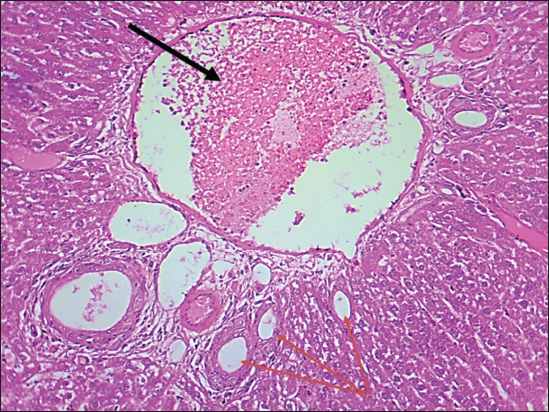

The results of this study revealed no significant differences in bilirubin levels in all treated animals (Table 1), whereas serum ALT and AST levels showed significant elevations in all treated animals either by citalopram alone (fourth group) or with J. regia pulp extract at doses of both 10 and 20 mg/kg (Tables 2 and 3). Sections of histopathological study appeared as mild degenerative lesions characterized by infiltration of fat droplets inside hepatic cells, which gave them a ring shape appearance due to pushing the nucleus at one side from the hepatic cells with fibrous networks formation in the tissue parenchyma, infiltration of structureless, homogenous, and pinkish material (Figs. 16). Clear hepatic vein congestion and narrowing in the hepatic artery and arteriole diameters revealed that citalopram caused liver dysfunction and injury (Figs. 79).

These results correspond with those of other studies, in which patients treated with antidepressants appeared to have moderately elevated levels of the aminotransferase. All antidepressants caused hepatotoxicity; citalopram is that have the least potential for hepatotoxicity, which is characterized by high alanine aminotransferase levels (Gartlehner et al., 2008; Voican et al., 2014; Ilgın et al., 2020). The results of this study revealed no significant differences in bilirubin levels in all treated animals as the level of p < 0.05, serum ALT and AST levels showed a significant elevation in all treated animals either by citalopram only (fourth group) or with J. regia pulp extract at doses of 10 and 20 mg/kg B.W. Sections of histopathological sections show mild degenerative lesions characterized by infiltration of fat droplets inside hepatic cells, which give them a ring shape appearance due to pushing the nucleus at one side from the hepatic cells with fibrous networks formation in the tissue parenchyma, infiltration of structureless, homogenous, and pinkish material (Figs. 4 and 6). Clear hepatic vein congestion and narrowing in the hepatic artery and arteriole diameters revealed that citalopram caused liver dysfunction and injury (Figs. 79).

Fig. 4. Histological section of the liver of rats drenched with 0.6 mg/kg citalopram. The section shows a mild degenerative lesion (fatty degeneration, black arrows) with fibrous network formation in parenchyma (red arrow), (H and E stain 100X).

Fig. 5. Histological section of the liver of rats drenched with 0.6 mg/kg citalopram. The section shows a mild degenerative lesion (fatty degeneration, black arrows), (H and E stain 100X).

Fig. 6. Histological section of the liver of rats drenched with 0.6 mg/kg citalopram. The section shows a mild fatty degenerative lesion in hepatic tissue characterized by the infiltration of fat droplets inside hepatic cells, which give them a ring-shaped appearance due to pushing the nucleus on the side from the hepatic cells (black arrows). The section shows infiltration of structureless, homogenous, and pinkish material (amyloidosis, red arrow) (H and E stain 100X).